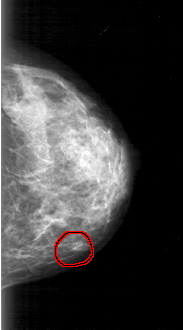

D_4031_1.LEFT_CC

LEFT_CC LINES 4936 PIXELS_PER_LINE 2731 BITS_PER_PIXEL 12 RESOLUTION 43.5 OVERLAY

FILE: D_4031_1.LEFT_CC.OVERLAY

TOTAL_ABNORMALITIES 1

ABNORMALITY 1

LESION_TYPE MASS SHAPE OVAL MARGINS OBSCURED

ASSESSMENT 0

SUBTLETY 5

PATHOLOGY BENIGN

TOTAL_OUTLINES 1

BOUNDARY